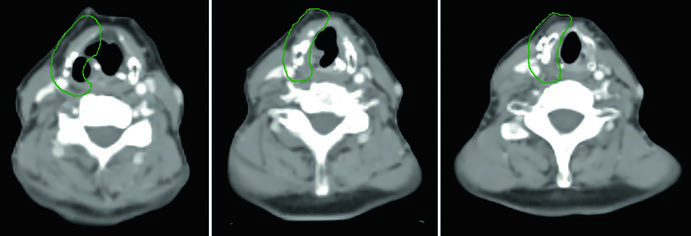

Caso 1 — Carcinoma papilar metastático (Fig. 9.1): Homem de 58 anos com carcinoma papilar metastático de tireoide, submetido a múltiplas ressecções prévias, que se apresentou com recorrência local irressecável e múltiplos linfonodos mediastinais. Recebeu quimiorradioterapia definitiva para prevenir progressão local. O CTV70 Gy (vermelho) abrange a recorrência local e linfonodos mediastinais envolvidos, enquanto o CTV60 Gy (verde) cobre as regiões subclínicas de risco. Este caso exemplifica o cenário de doença recorrente que esgotou as opções cirúrgicas — a radioterapia com dose definitiva é a melhor alternativa para controle local.